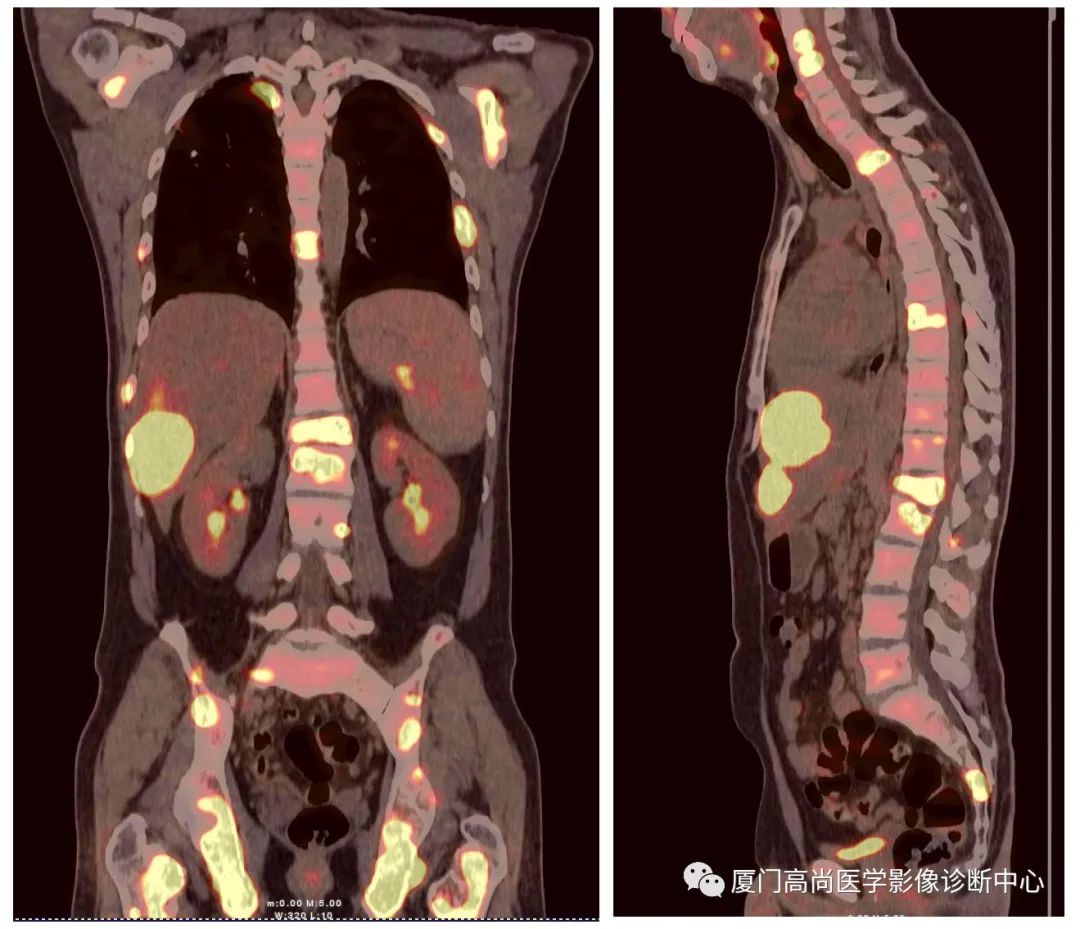

淋巴瘤在骨骼、肝臟、脾臟、淋巴結(jié)表現(xiàn)

肝臟、脾臟、骨骼淋巴瘤病灶

骨骼、腋窩淋巴結(jié)病灶

PET/CT發(fā)現(xiàn) :全身多發(fā)淋巴結(jié)腫大,F(xiàn)DG攝取增高;肝臟、脾臟多發(fā)低密度結(jié)節(jié), FDG攝取增高;雙側(cè)扁桃體腫大,F(xiàn)DG攝取增高;全身多處骨骼破壞,F(xiàn)GD攝取增高;上述考慮為淋巴瘤

經(jīng)淋巴結(jié)穿刺活檢 :病理診斷為彌漫大B細(xì)胞淋巴瘤